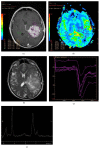

Primary Central Nervous System Lymphoma (PCNSL) is a rare neoplasm that can involve brain, eye, leptomeninges, and rarely spinal cord. PCNSL lesions most typically enhance homogeneously on T1-weighted magnetic resonance imaging (MRI) and appear T2-hypointense, but high variability in MRI features is commonly encountered. Neurological symptoms and MRI findings may mimic high grade gliomas (HGGs), tumefactive demyelinating lesions (TDLs), or infectious and granulomatous diseases. Advanced MRI techniques (MR diffusion, spectroscopy, and perfusion) and metabolic imaging, such as Fluorodeoxyglucose Positron Emission Tomography (FDG-PET) or amino acid PET (usually employing methionine), may be useful in distinguishing these different entities and monitoring the disease course. Moreover, emerging data suggest a role for cerebrospinal fluid (CSF) markers in predicting prognosis and response to treatments. In this review, we will address the challenges in PCNSL diagnosis, assessment of response to treatments, and evaluation of potential neurotoxicity related to chemotherapy and radiotherapy.